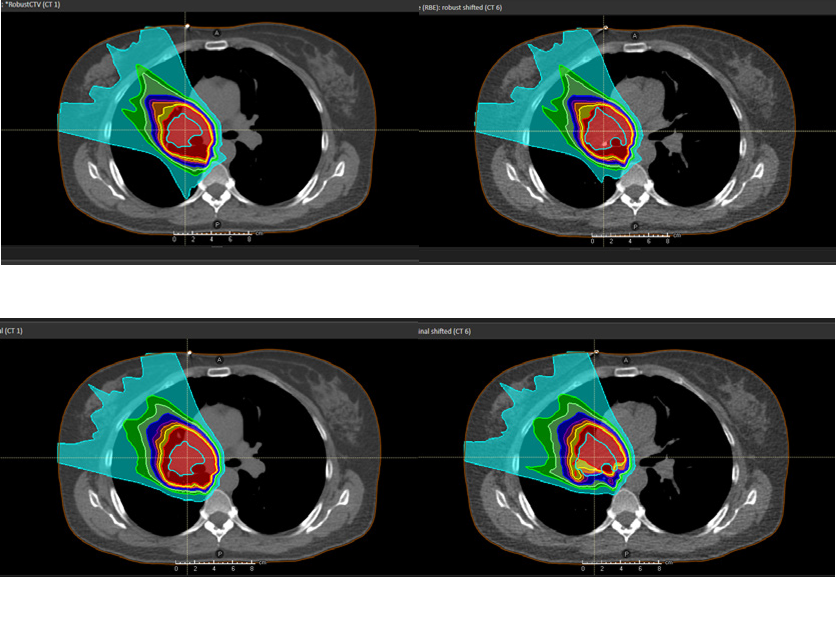

Example 1 (Figure 2)

Robust optimization for IMPT applied to a 4D-CT lung case subject to at most 0.5 cm setup errors and 3.0 % density errors was compared to margin-based planning. The ten phases of the 4D-CT were included in the robust optimization. Transversal slices of the planning CT (CT 1) under the nominal scenario and of a non-planning CT (CT 6) under a perturbed scenario are shown in Figure 2. The figure illustrates that robust optimization can lead to improved robustness at the same time as decreased integral dose compared to conventional margins.

Figure 2